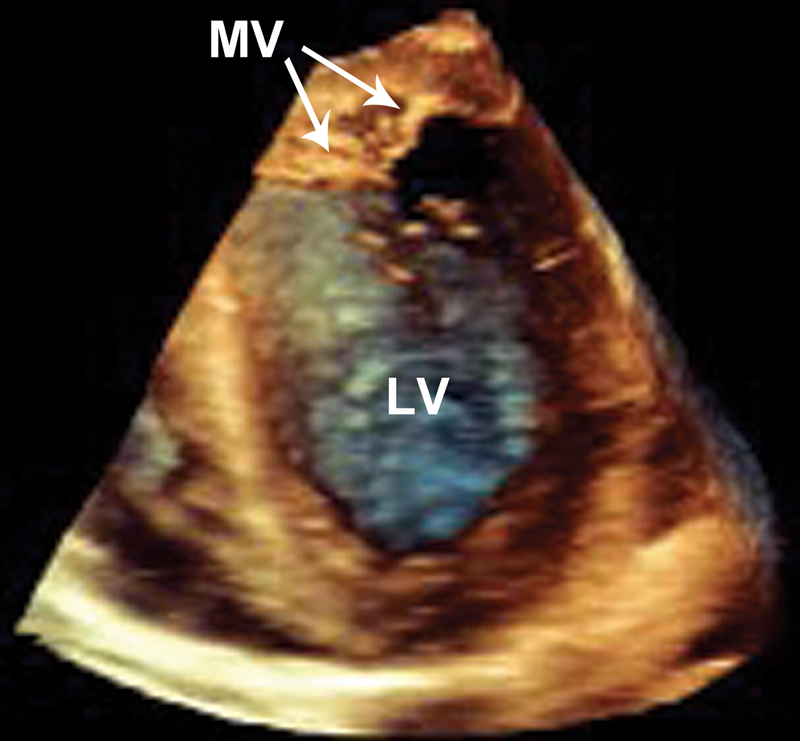

فحوصات تشخيصية لبعض امراض القلب والشرايين التاجية